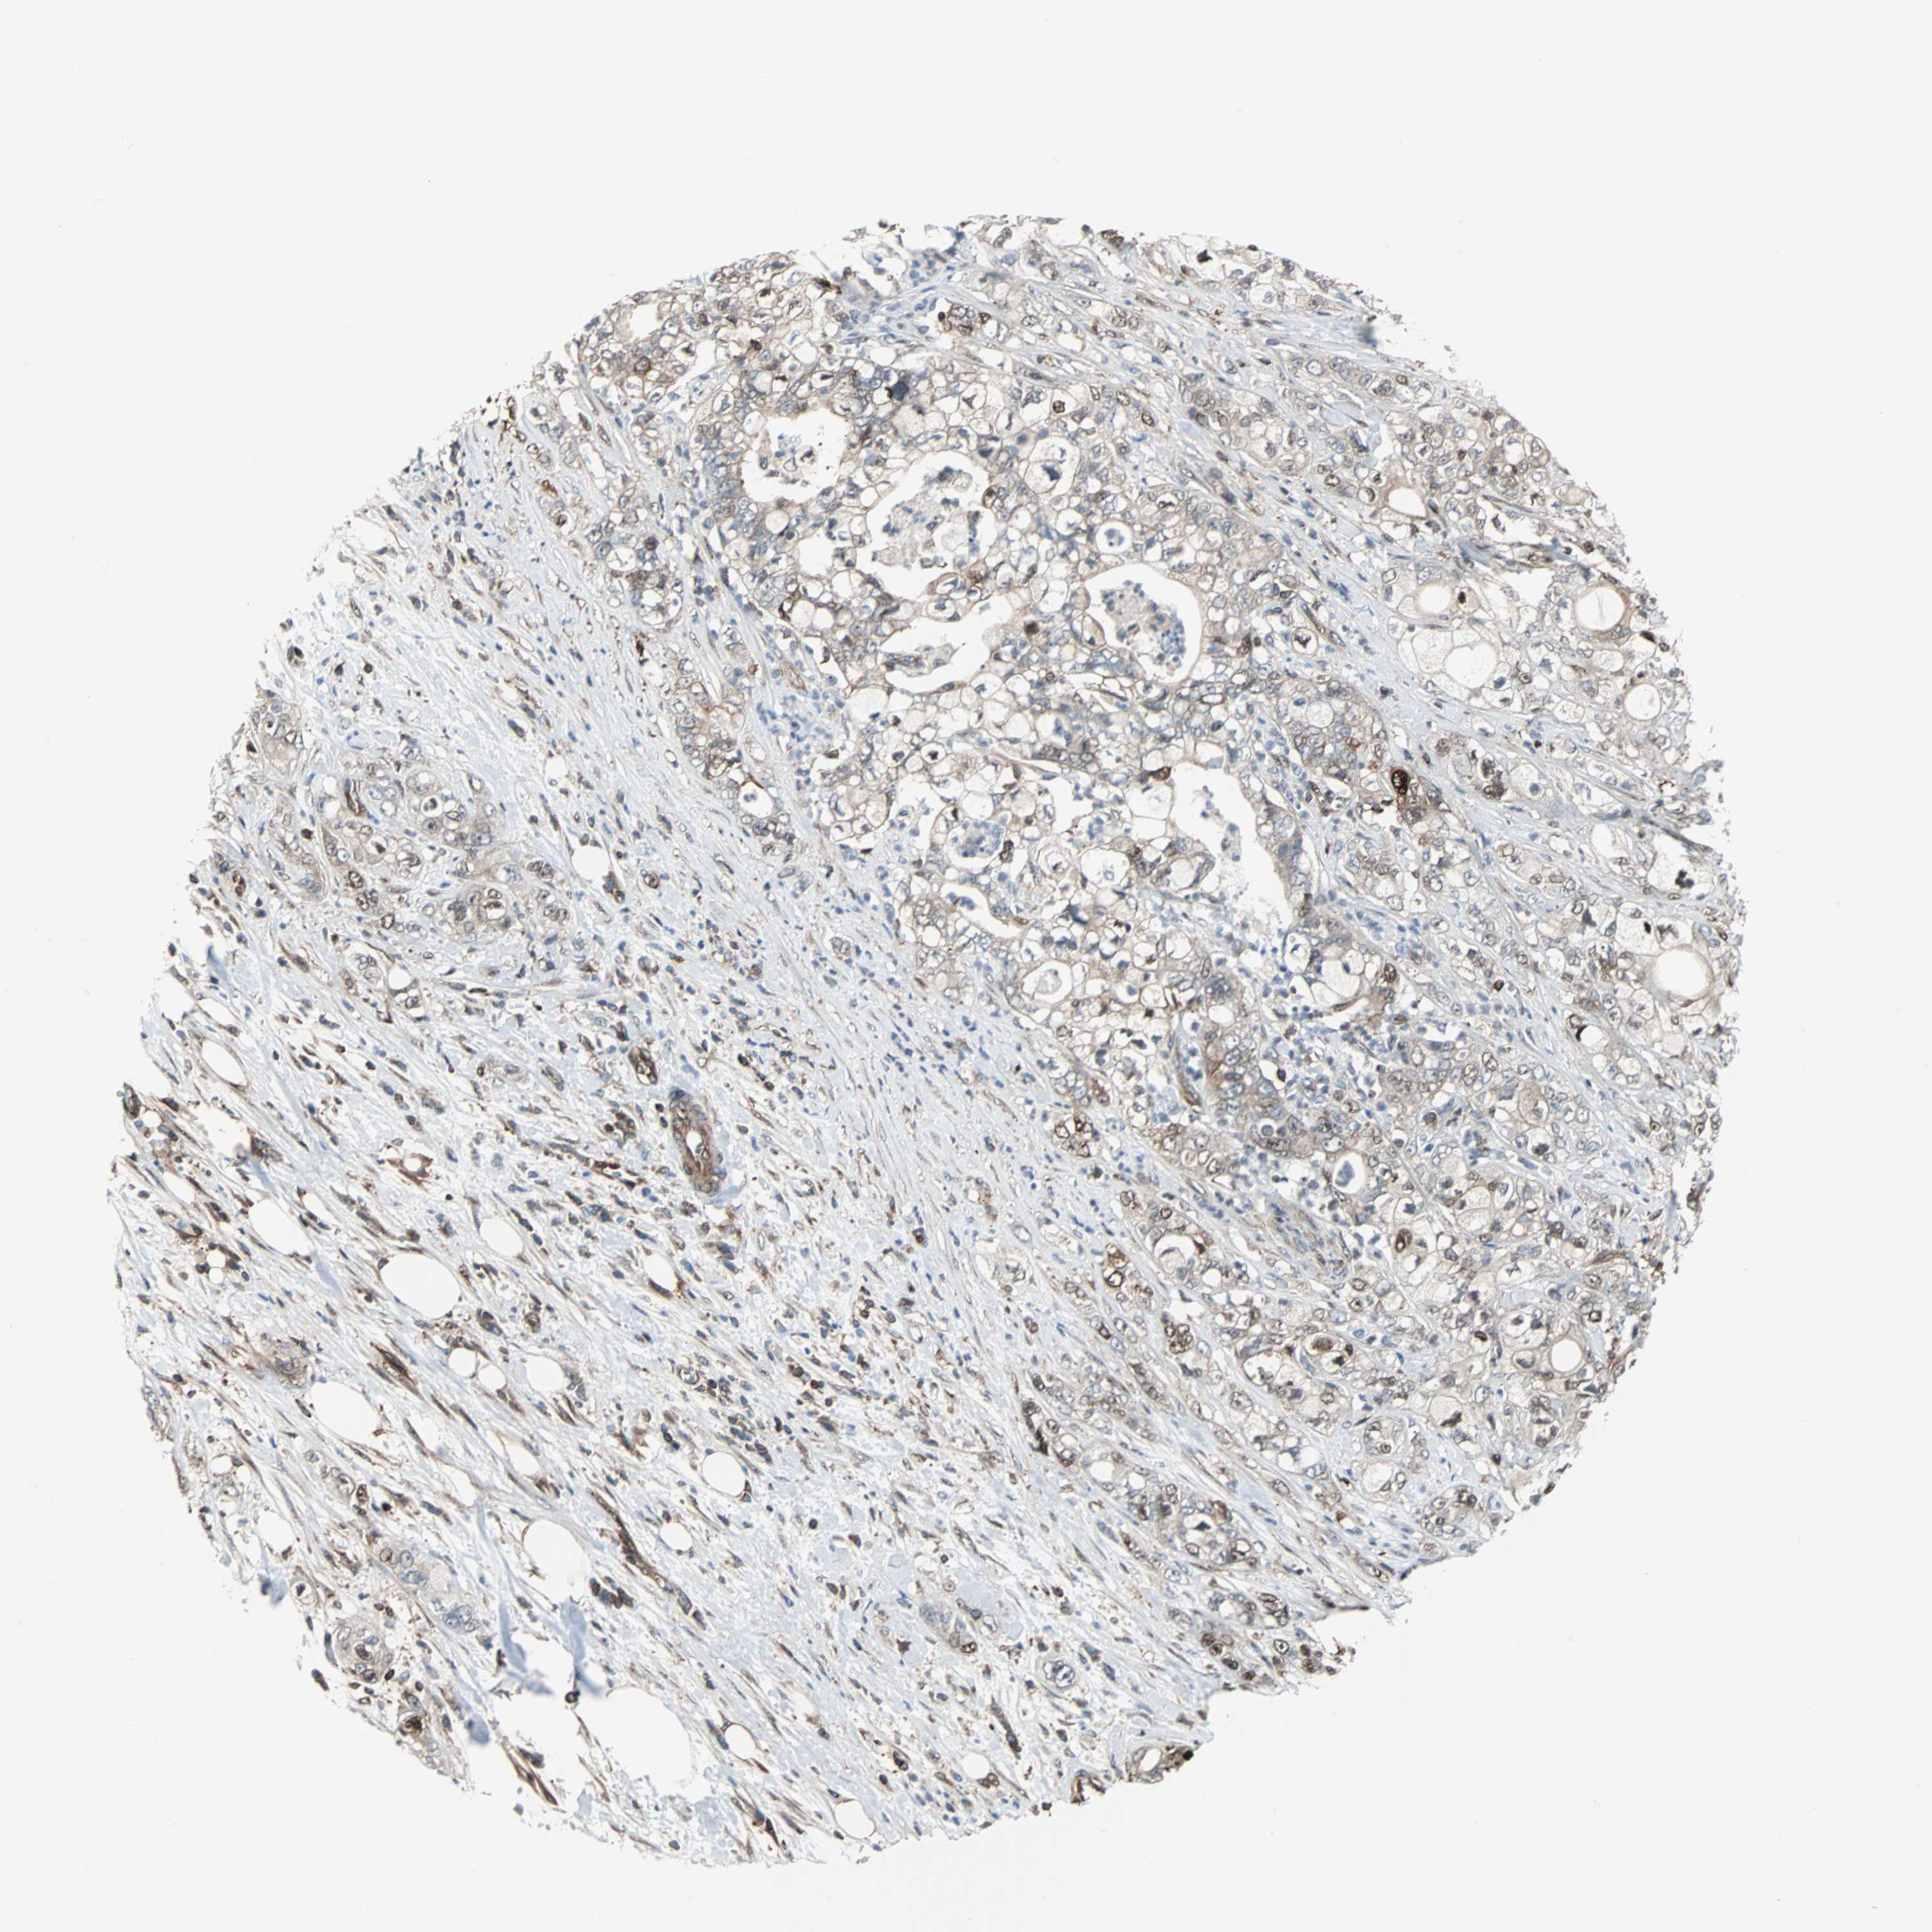

PANCREATIC CANCER - Protein expressioni

A mouse-over function shows sample information and annotation data. Click on an image to view it in a full screen mode. Samples can be filtered based on level of antibody staining by selecting one or several of the following categories: high, medium, low and not detected. The assay and annotation is described here.

Note that samples used for immunohistochemistry by the Human Protein Atlas do not correspond to samples in the TCGA dataset.

Antibody stainingi

Antibody staining in the annotated cell types in the current human tissue is reported as not detected, low, medium, or high, based on conventional immunohistochemistry profiling in selected tissues. This score is based on the combination of the staining intensity and fraction of stained cells.

Each image is clickable and will lead to virtual microscopy that enables deeper exploration of all samples and also displays staining intensity scores, fraction scores and subcellular localization as well as patient and tissue information for each sample.

Antibody CAB004264

Antibody CAB005030

Staining

High

Medium

Low

Not detected

Intensity

Strong

Moderate

Weak

Negative

Quantity

>75%

75%-25%

<25%

None

Location

Nuclear

Cytoplasmic/membranous

Cytoplasmic/membranous,nuclear

Adenocarcinoma, NOS